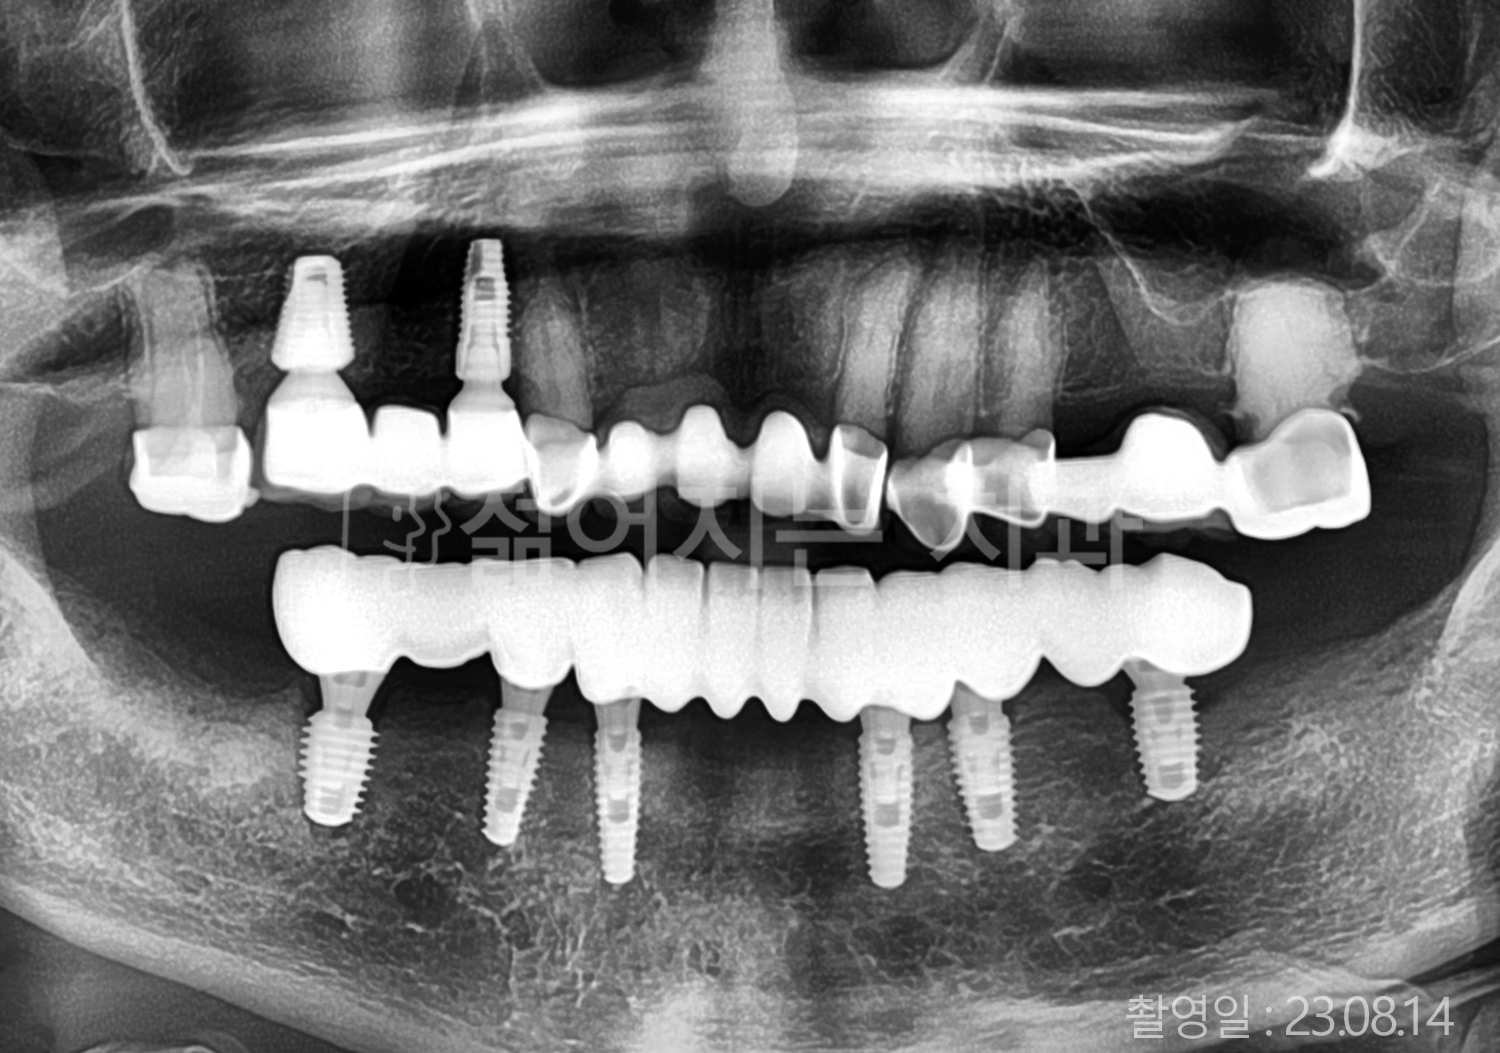

• 70대 고혈압, 고지혈증 전체치아 10개 이상 임플란트

• 60대 당뇨, 간염 전체치아 10개 이상 임플란트

• 80대 골다골증 전체치아 6개 이상 임플란트

• 70대 고혈압, 당뇨 전체치아 10개 이상 임플란트

• 60대 간 질환 전체치아 10개 이상 임플란트

• 60대 전체치아 10개 이상 임플란트

• 70대 전체치아 10개 이상 임플란트

• 50대 전체치아 10개 이상 임플란트

• 60대 고혈압, 고지혈증 전체치아 10개 이상 임플란트

• 40대 고지혈증, 뇌혈관 질환 전체치아 10개 이상 임플란트